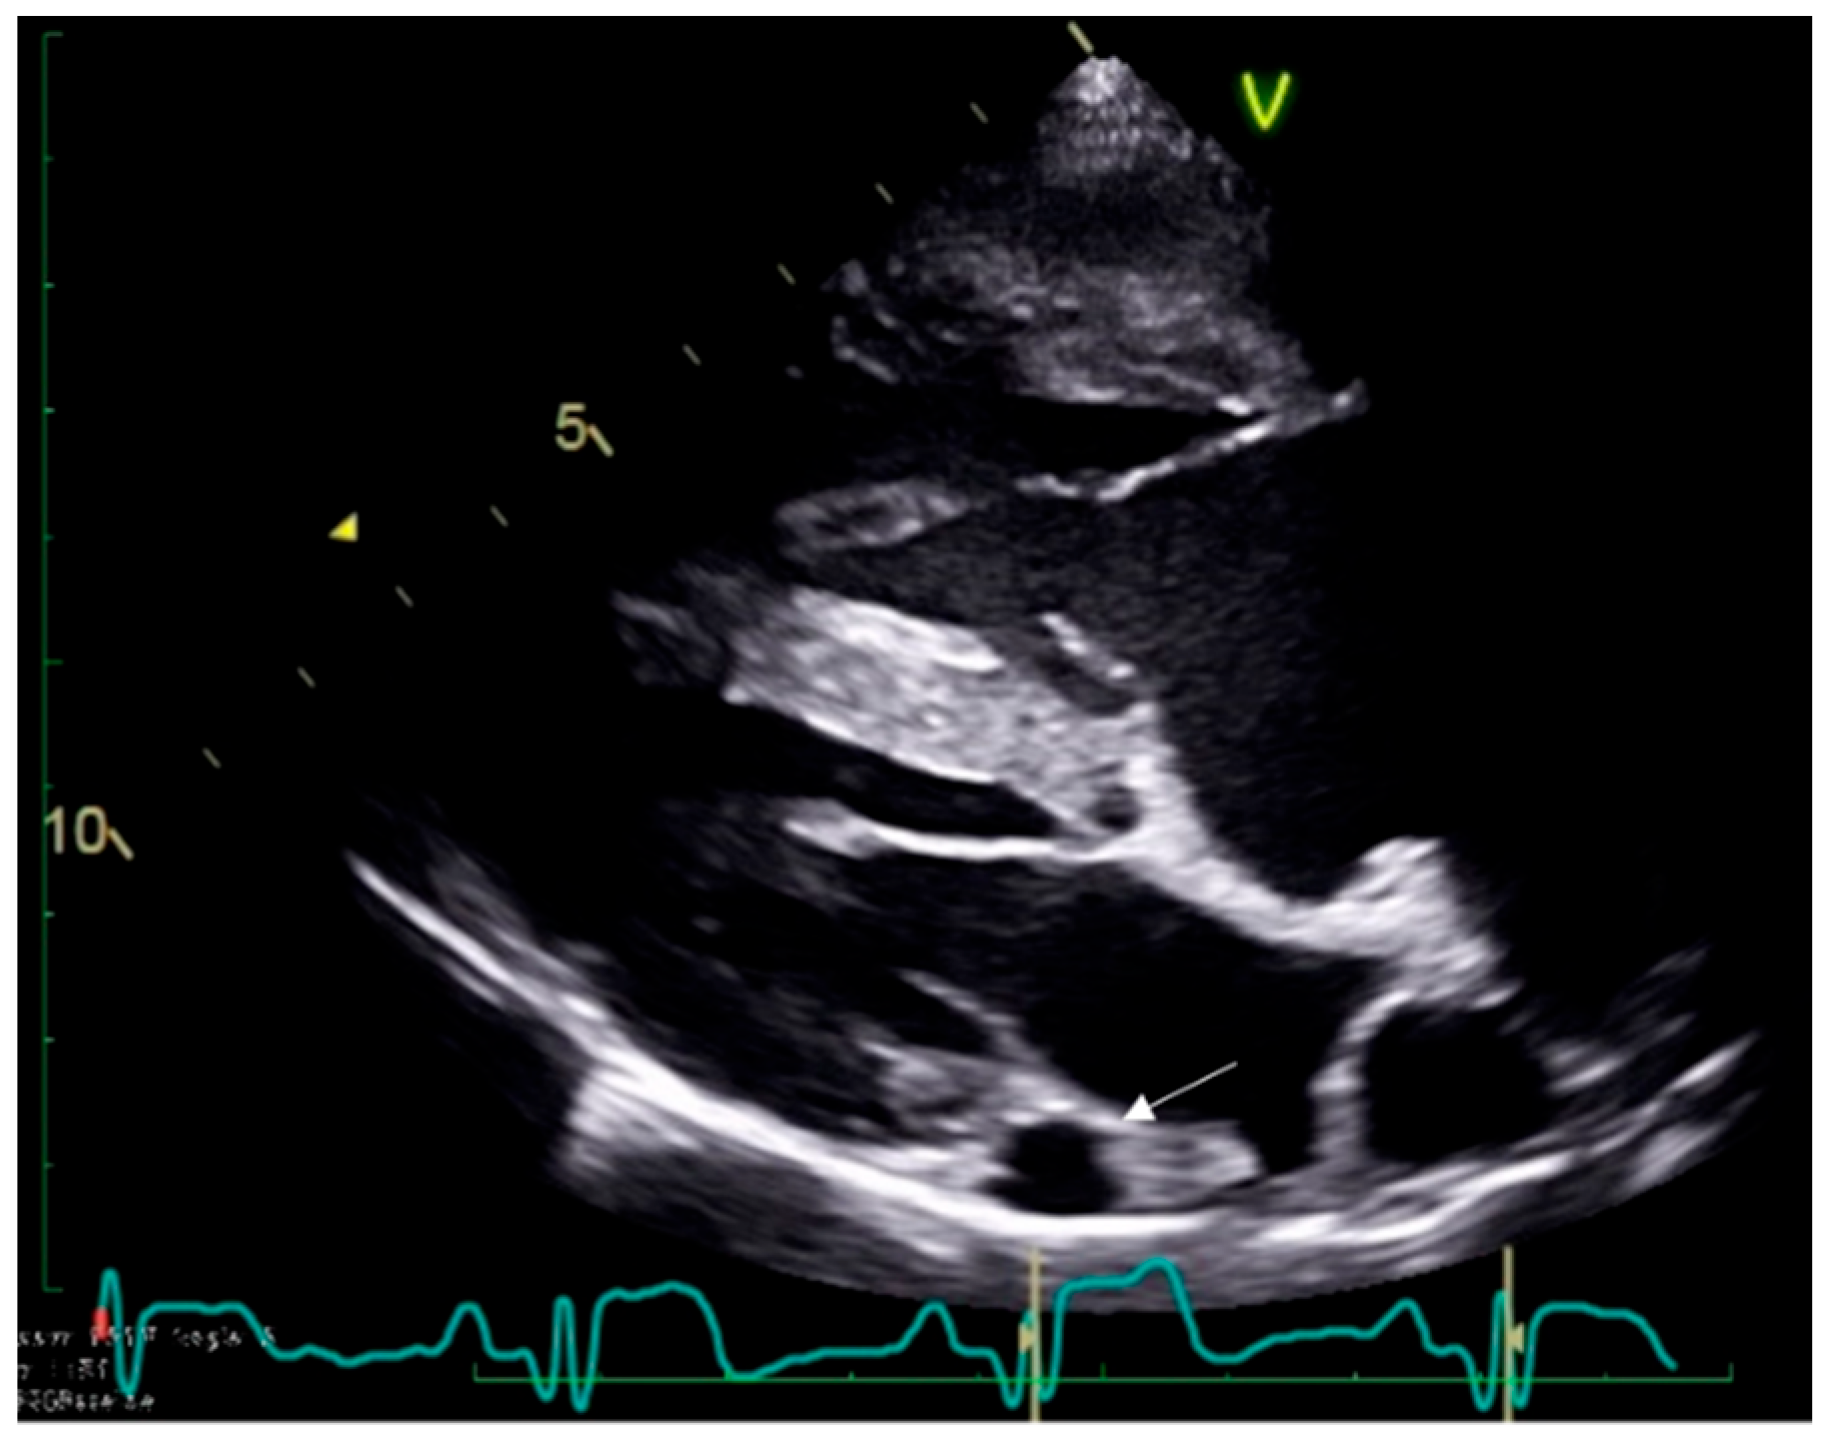

2.1. Case 1

2.2. Case 2

2.3. Case 3